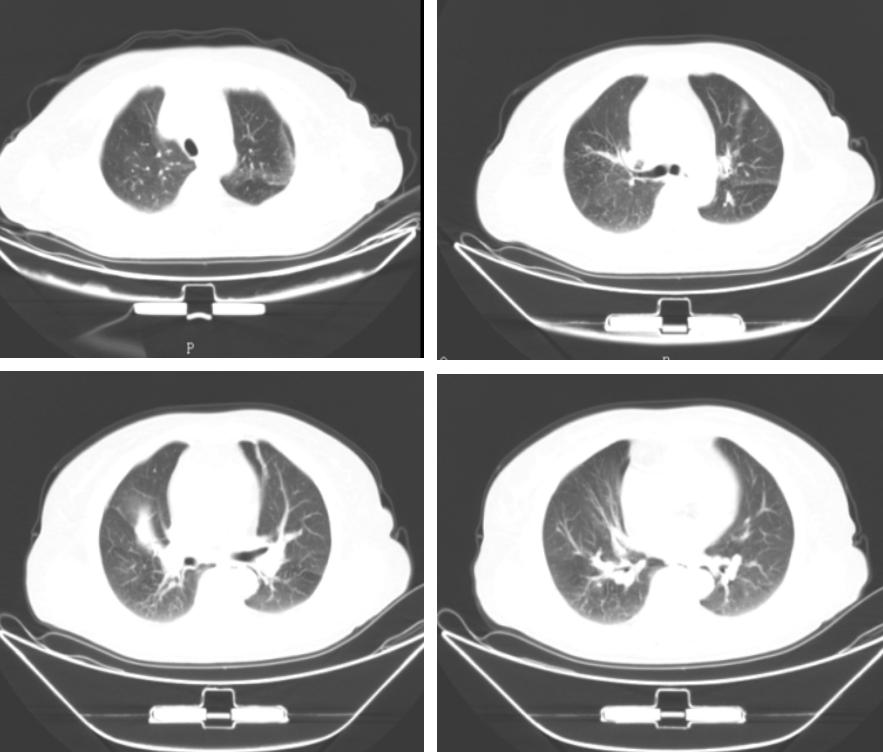

我们首先回顾一下该患者10年前的第一次住院情况。患者自发病以来神志清晰,精神尚可,食欲和睡眠都正常,二便正常。其既往史、个人史、婚育史、家族史均无特殊。对其进行体格检查情况为:入院查体:T36.0℃, P 72次/分, R 16次/分, BP 115/70mmHg,神志清,精神可。全身皮肤黏膜正常,无皮疹及皮下结节;全身浅表淋巴结未触及肿大。胸廓正常,双肺呼吸音稍粗,未闻及干湿啰音,心律齐,各瓣膜听诊区未闻及病理性杂音。辅助检查情况为:胸部CT提示:双肺纹理粗乱,右肺中叶支气管狭窄,右肺中叶高密度影。(图1)

图1:第一次入院胸部CT